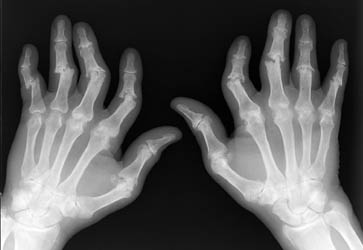

Psoriatic arthritis is an asymmetric process primarily with distal involvement of the hands. There are five different patterns of psoriatic arthropathy which are described in the following section. It is important to note that patients will usually exhibit findings which include more that one of these subsets.

Erosions will usually begin at the peripheral articular surfaces and extend

centrally. Fluffy bone periostitis and erosions at the interphalangeal joints

can create an appearance which resembles "mouse ears".

As previously mentioned, there are five different patterns of psoriatic arthritis. Classic psoriatic arthritis or DIP arthritis, involves the distal digits with associated fingernail pathology. Resorption of the distal phlangeal tufts can often be seen; this is a process called acroosteolysis. Arthritis mutilans, is a very destructive form of psoriatic arthritis with significant periarticular bone resorption. The erosions can cause a "pencil in cup" deformity where one articular surface is eroded creating a pointed appearance; the articulating bone can be concave, resembling an upside down cup. Symmetric polyarthropathy, can strongly resemble rheumatoid arthritis with erosions and ankylosis of the interphalangeal joints. Asymmetrical oligoarthritis, has the appearance of soft tissue swelling of a single phalanx known as a "sausage digit". The fifth and last pattern exhibits findings similar to ankylosing spondylitis with spinal sendesmophytes which occur in an asymmetric distribution. This is associated with sacroilitis which will usually present in an asymmetric and unilateral pattern.

Radiographic findings of the hand in an asymmetrical distribution distally

without periarticular osteoporosis can help to differentiate psoriatic arthritis

from rheumatoid arthritis. Overlapping patterns of the two disease processes